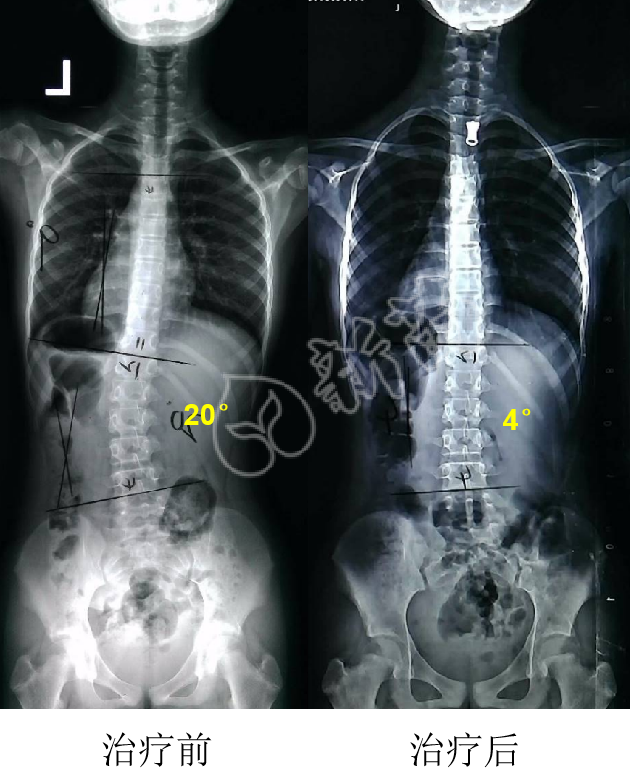

我是怎么从脊柱侧弯20度减到4度的

图片尺寸631x782